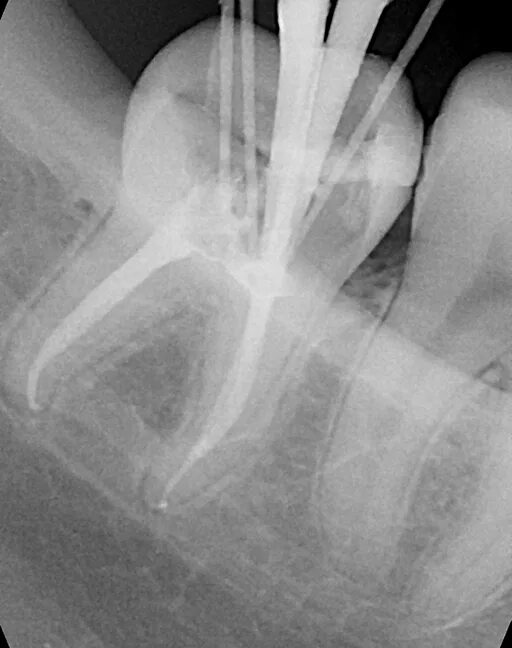

Пломбирование перфорации